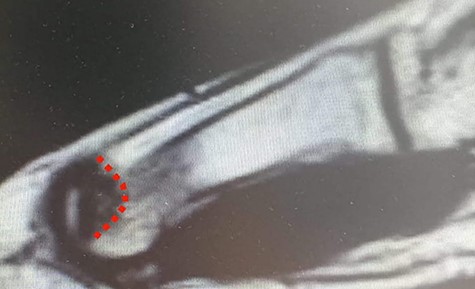

MRI (sagittal view) of the left foot. The red dots show a deep MH defect involving the subchondral bone, a typical finding of OD.

Standing anteroposterior (AP), oblique and lateral radiographs of the affected foot were taken. On the AP and oblique views, an OD lesion of the 1st MH was visible (lytic lesion of the subchondral bone and subchondral sclerosis formation) with a lateral-forming osteophyte (Fig. 1A and B). Magnetic resonance imaging (MRI) of the left foot clearly shows the osteochondral defect of the 1st MH (Figs 2 and 3).